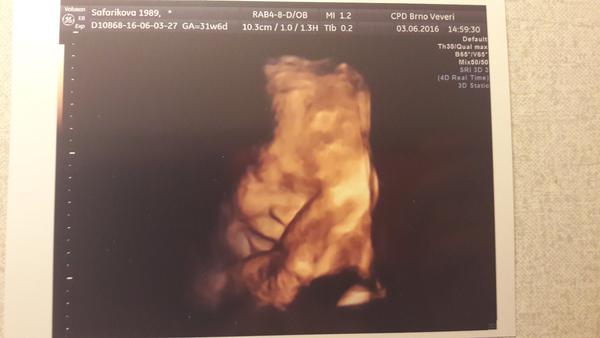

slunicko156 : Ahoj, ja u nej byla na e.ultrazvuku a parada 🙂 Byla jsem nejspokojenejsi ze vsech navstev, byl moc ochotny a mily. Chteli jsme barevnou fotku za 200Kc, jako delali vzdycky (proste klasicka z ultrazvuku akorat na fotopapire a barevna), ale on nam to prepnul do 3D a jeste udelal nekolik variant, abysme si vybrali 🙂 A byla taky za 200Kc, byla jsem nadsena!